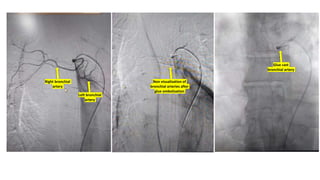

The document details a series of vascular procedures, including recanalization of the peroneal artery, medial plantar artery, and right brachiocephalic vein following occlusions. It also mentions angioplasty and the presence of abnormal blood flow in various uterine and bronchial arteries, along with complications like CBD obstruction due to a periampullary adenocarcinoma. Additional notes on venous collaterals and their disappearance are included.